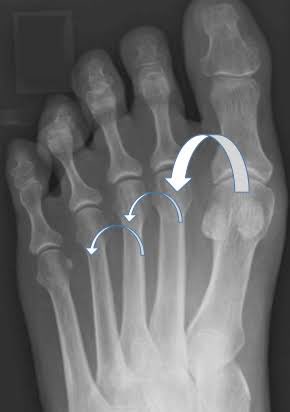

٥-متلازمة فرايبورغ:

عبارة عن نقص في التروية الدموية لمفصل قاعدة الأصابع ولا يعرف حتى الآن السبب الرئيسي لذلك

👈🏻يصيب النساء اكثر من الرجال بأربع مرات بين ١٤-١٨ سنة، خصوصاً من يمارسون الرياضة بشكل كبير ومستمر

بالأشعة المرفقة يلاحظ وجود تآكل في رأس المفصل لضعف التروية الدموية.